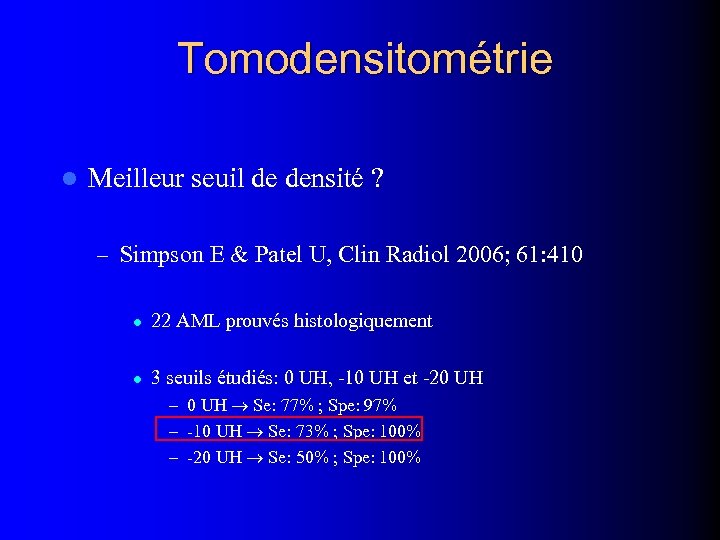

Tomodensitométrie l Meilleur seuil de densité ? – Simpson E & Patel U, Clin Radiol 2006; 61: 410 l 22 AML prouvés histologiquement l 3 seuils étudiés: 0 UH, -10 UH et -20 UH – 0 UH Se: 77% ; Spe: 97% – -10 UH Se: 73% ; Spe: 100% – -20 UH Se: 50% ; Spe: 100%

Tomodensitométrie l Meilleur seuil de densité ? – Simpson E & Patel U, Clin Radiol 2006; 61: 410 l 22 AML prouvés histologiquement l 3 seuils étudiés: 0 UH, -10 UH et -20 UH – 0 UH Se: 77% ; Spe: 97% – -10 UH Se: 73% ; Spe: 100% – -20 UH Se: 50% ; Spe: 100%